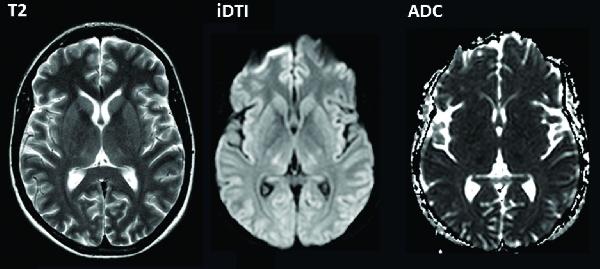

Ebenfalls um einen Transregio-SFB, also einen von mehreren Hochschulen gemeinsam beantragten Verbund, handelt es sich auch bei dem SFB TRR 128 zu den „Initiierungs-, Effektor- und Regulationsmechanismen bei Multipler Sklerose“ (MS). Sprecher dieser Kooperation zwischen den Hochschulen Münster, Mainz und München wird ab Juli Prof. Heinz Wiendl von der münsterschen Uniklinik für Allgemeine Neurologie; als Co-Sprecherin fungiert dann Prof. Frauke Zipp von der Universitätsmedizin Mainz. MS stellt die häufigste entzündliche Erkrankung des zentralen Nervensystems dar und betrifft vor allem jüngere Menschen. Da die Krankheit einen sehr ungleichmäßigen Verlauf hat, können Ärzte ihren Patienten keine verlässliche Prognose stellen.

Unter dem Dach des SFB TRR 128 arbeiten daher seit 2012 erstmals in Deutschland Neurowissenschaftler gemeinsam daran, die krankhaften Mechanismen von MS im Körper zu entschlüsseln und die Therapiemöglichkeiten zu verbessern. Zwar ist die Erkrankung nicht heilbar, sie lässt sich jedoch durch Medikamente positiv beeinflussen. „Bereits in der ersten Förderperiode konnten wir große Fortschritte erzielen beim Verständnis des komplexen Zusammenspiels zwischen Immun- und Nervensystem“, kommentiert Prof. Wiendl die Bewilligung der DFG von knapp 15,3 Mio. Euro. Die zweite Förderperiode beinhaltet auch neuartige Projekte, die die Rolle von Umweltfaktoren wie Sonneneinstrahlung und Ernährung untersuchen, inklusive damit verbundener Therapieansätze.